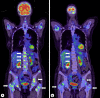

Bone marrow carcinomatosis (BMC) associated with breast cancer is a rare but often difficult-to-treat condition; we report a case of a female stage IV breast cancer patient in her seventies with BMC that improved with endocrine monotherapy. The patient had hemoglobinopenia and thrombocytopenia at the time of diagnosis. The diagnosis of BMC due to estrogen receptor-positive invasive lobular carcinoma was confirmed. After transfusion of 4 units of concentrated red blood cells, endocrine treatment with letrozole improved the hematopenia. Ten months after the treatment started, bone metastases worsened, so the patient was changed to combination therapy with palbociclib and fulvestrant, after which there was no worsening of the disease.